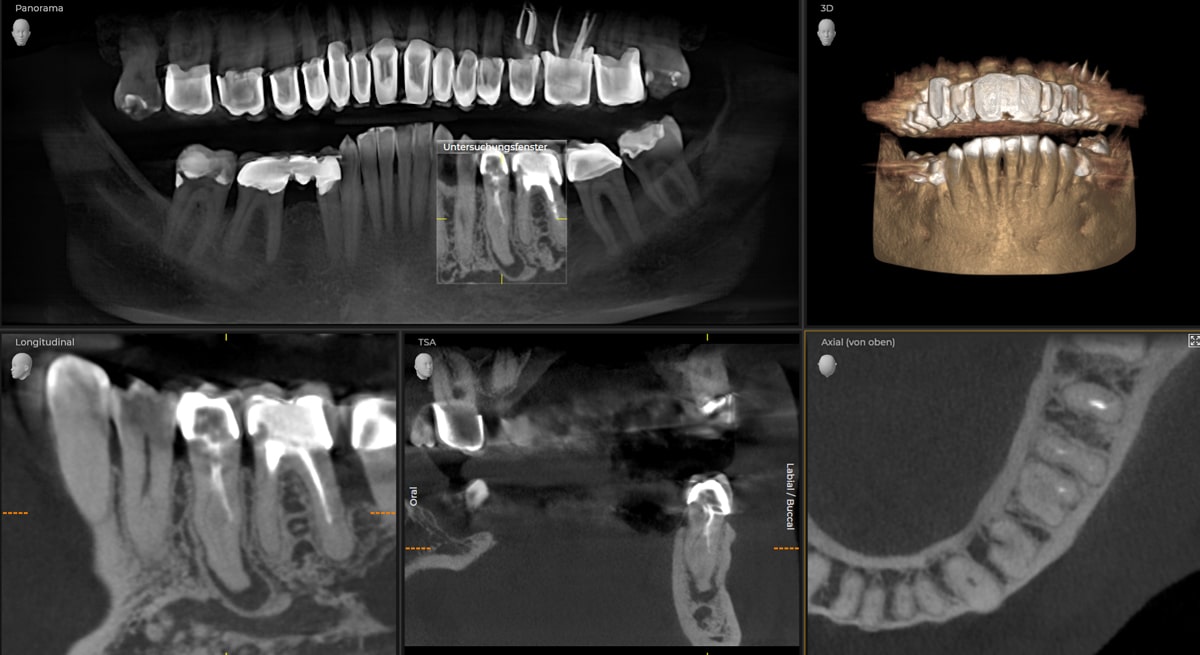

Komplexe Anatomie Zähne 25 und 35